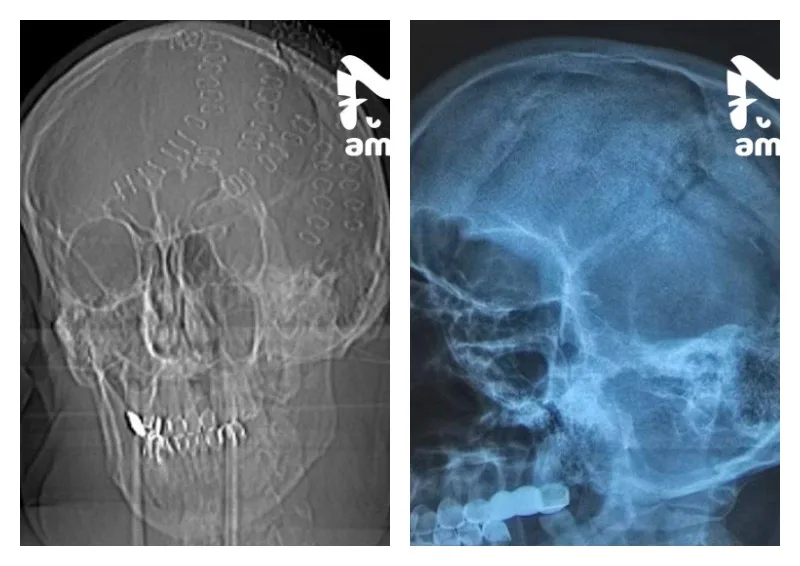

Мужчину с острова Попова доставили в больницу с тяжелейшими травмами головы — множественные вдавленные переломы темени, ушиб мозга, обширное кровоизлияние и резаные раны. Он находился в шоковом состоянии. Об этом пишет тг-канал Amur Mash.

Хирурги экстренно провели многочасовую операцию, во время которой удалили фрагменты разрушенного черепа. Пациента удалось стабилизировать.